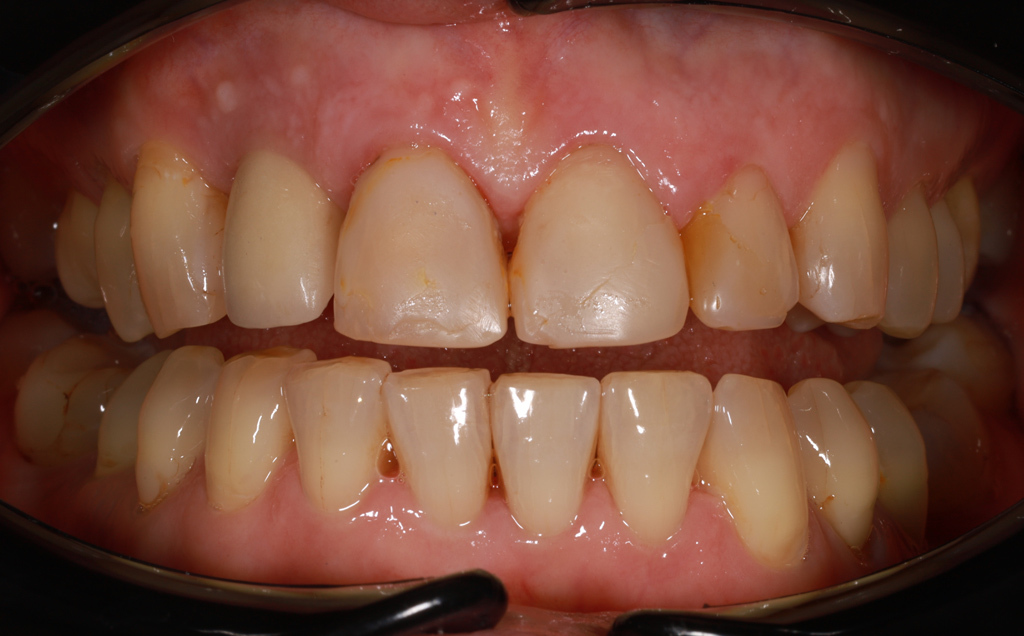

Zaprezentujemy serię poruszających historii pacjentów, którzy zdecydowali się na kompleksowe leczenie dentystyczne. Od przypadków zaawansowanej próchnicy, przez wypadki, które wymagały rekonstrukcji zębów, po pacjentów marzących o hollywoodzkim uśmiechu dzięki zastosowaniu licówek – każda historia jest dowodem na to, jak nowoczesna stomatologia może odmienić życie.

Metamorfoza uśmiechu: usunięcie przebarwień i kamienia nazębnego.

Poprawa estetyki uśmiechu: wybielanie zębów.